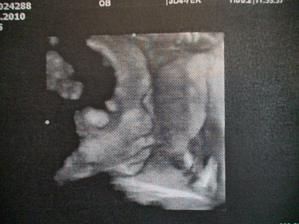

velký utz 2.6.(30tt+4) dopadl výborně, váhový odhad 1823g🙂 malá je hlavou dolů, obličejem na pravou stranu, dle hlavičky odpovídáme tt těhotenství, dle váhy jsme o týden větší🙂) placenta na zadní stěně. Doktor kontroloval srdíčko, ledviny, žaludek, páteř..měřil stehenní kost. ukazoval nám obličej na 2D utz-byly nádhreně vidět rtíky a nosík🙂 takže žádné rozštěpy nebo jiná nemilá překvápka🙂 a dostali sme i 3D fotečku. Sice jen půlku obličeje, pže plod vody už je ve 31tt méně, ale stejně je nááádherná🙂 Jo a pohlaví nám ukazoval, je tam děvčátko nad vší pochybnost🙂